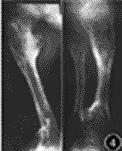

Maffucci综合征是指内生软骨瘤病海绵状血管瘤同时存在。Maffucci于1881年首先描写。

患者身上内生软骨瘤与内生软骨瘤病(亦即软骨发育者异常或ollier病)无任何区别。血管瘤则绝大多数为海绵状血管瘤,质软,多叶,无血管性搏动。亦有为毛细血管瘤淋巴管瘤以及血管错构瘤的报告往往伴有静脉曲张静脉栓塞静脉石形成。

常为双侧性,但单侧比较明显。常见于掌骨指骨(87.8%)。病人智力发充正常,但身材较短小,约有12%的患者为侏儒,并且常有下肢不等长(36%)。有时可见拐状手,膝内翻髋内翻扁平足继发性畸形。肢体的功能常因肿瘤而受损。骨骼病变常与血管瘤无直接关,即两者可以分别发生在不同的肢体。不产生疼痛。患者的内生软骨瘤的恶变率可达15.2~18.6%,而且在同一个病人身上可有数处发生恶变。血管瘤亦有恶变的报告。如果肿瘤范围扩大,以及在无外伤的情况下出现疼痛,均应及时活检。